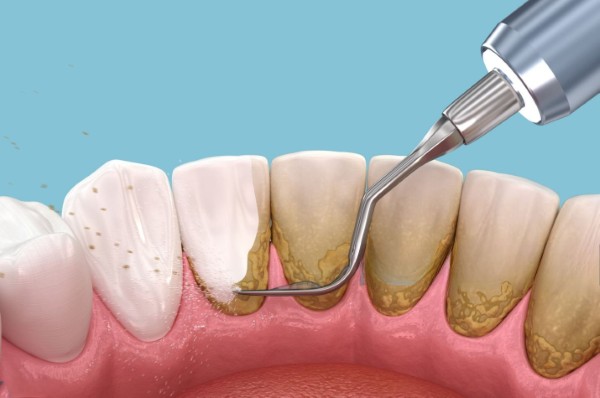

Quá trình hình thành cao răng

Quá trình hình thành cao răng diễn ra khá nhanh chóng:

- Mảng bám: Khi chúng ta ăn uống, vi khuẩn tạo ra mảng bám trên bề mặt răng.

- Canxi hóa: Nếu không được làm sạch trong khoảng thời gian 24-72 giờ, mảng bám sẽ bắt đầu hình thành các tinh thể canxi, dẫn đến cao răng.